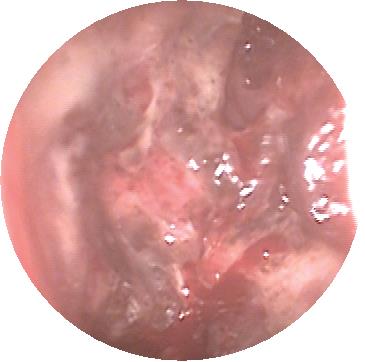

• 博来霉素多点注射联合介入栓塞治疗眼眶血管畸形的临床研究

2025, 35(17):61-66. DOI: 10.3969/j.issn.1005-8982.2025.17.010

摘要 (162) HTML (42) PDF 912.73 K (88) 评论 (0) 收藏

摘要:目的 评估博来霉素多点注射联合介入栓塞治疗在治疗眼眶血管畸形中的临床疗效及安全性。方法 选取2020年1月—2023年12月在中国人民解放军陆军第七十三集团军医院接受治疗的115例眼眶血管畸形患者为研究对象。随机分为两组,对照组(57例)接受经导管动脉硬化栓塞治疗,治疗组(58例)接受博来霉素多点注射联合经导管动脉硬化栓塞治疗。采用数字减影血管造影指导介入治疗,并通过临床症状改善情况、瘤体面积变化、瘤体厚度变化、影像学评估及不良反应发生率等评价治疗效果。结果 治疗组的总有效率达到100%,高于对照组的85.96%(P <0.05)。治疗组治疗前后瘤体面积与瘤体厚度的差值均大于对照组(P <0.05)。影像学评估显示,治疗后眼眶血管畸形显著缩小,周围肿胀组织逐步恢复至正常状态。治疗组和对照组的不良反应发生率分别为3.44%和8.77%,差异无统计学意义(P >0.05)。两组均无严重并发症报告。结论 博来霉素多点注射联合经导管动脉硬化栓塞治疗在改善眼眶血管畸形临床症状和减小瘤体尺寸方面表现出显著优势,并且不良反应发生率较低,是一种有效且安全的治疗策略。